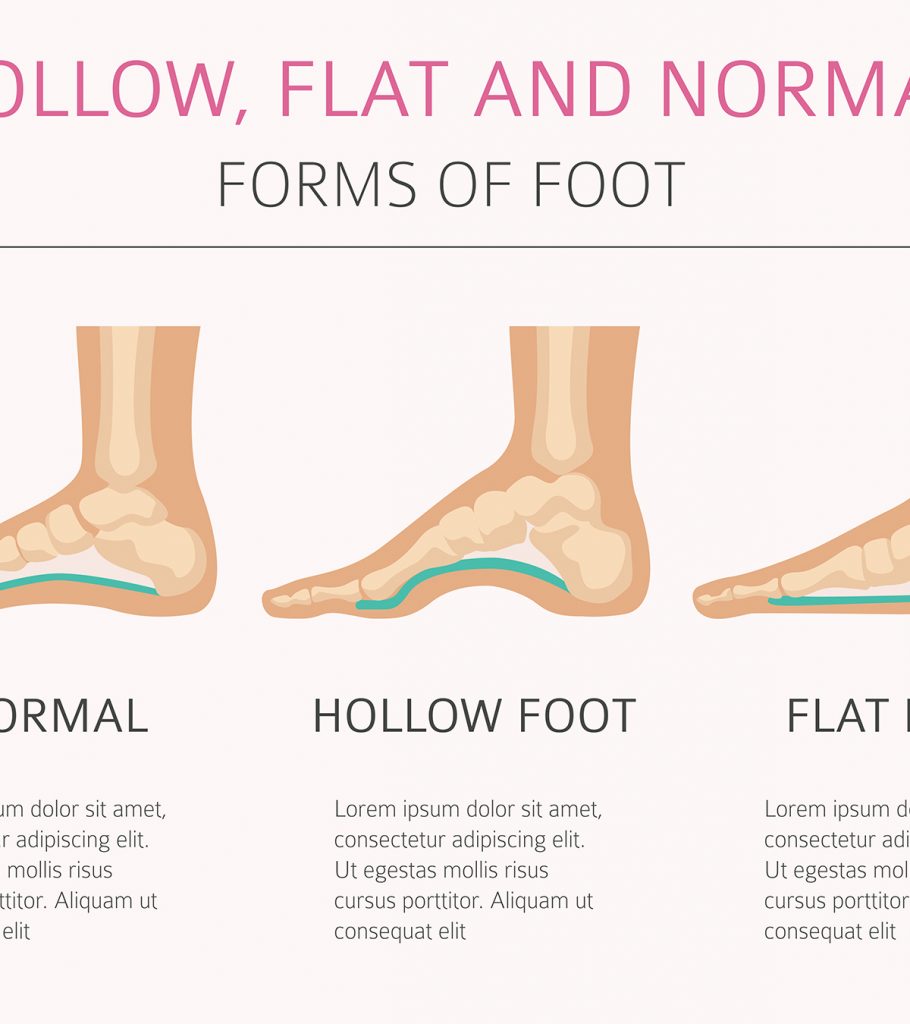

pictures of flat feet

Foot Postures: What It Means for Your Feet?

FLAT FOOT- Definition, Symptoms, Causes & Rehabilitation Exercises

Flat Feet and High Arched Feet | Things to Know – Custom Rehab

Flat Foot: Symptoms, Causes And Treatment Of Pes Planus